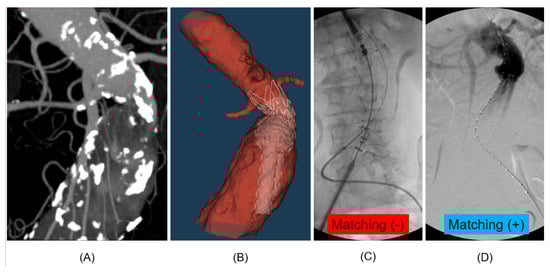

Digital Twin and Artificial Intelligence Technologies to Assess the Type IA Endoleak

Bioengineering 2026, 13(1), 1; https://doi.org/10.3390/bioengineering13010001 - 19 Dec 2025

Background/Objectives: Endovascular aneurysm repair (EVAR) is the standard treatment for abdominal aortic aneurysms, but the risk of endoleak compromises its effectiveness. Type IA endoleak, stemming from an inadequate proximal seal, is the most critical complication associated with the highest risk of rupture. Current [...] Read more.

Background/Objectives: Endovascular aneurysm repair (EVAR) is the standard treatment for abdominal aortic aneurysms, but the risk of endoleak compromises its effectiveness. Type IA endoleak, stemming from an inadequate proximal seal, is the most critical complication associated with the highest risk of rupture. Current preoperative planning relies on static anatomical measurements from computed tomography angiography that fail to predict seal failure due to dynamic biomechanical forces. This study aimed to retrospectively validate the predictive accuracy of a novel physics-informed digital twin and artificial intelligence (AI) model for predicting type IA endoleak risk compared to conventional static planning methods. Methods: This was a retrospective, single-center proof-of-concept validation study involving 15 patients who underwent elective EVAR (5 with confirmed type IA endoleak and 10 without type IA endoleak). A patient-specific digital twin was created for each case to simulate stent-graft deployment and capture the dynamic biomechanical interaction with the aortic wall. A logistic regression AI model processed over 16,000 biomechanical measurements to generate a single, objective metric of the endoleak risk index (ERI). The predictive performance of the ERI (using a cutoff of 0.80) was assessed and compared against a 1:3 propensity score-matched conventional control group (n = 45) who received traditional anatomical-based planning. Results: The mean ERI was significantly higher in the endoleak-positive group (0.85 ± 0.10) compared to the endoleak-negative group (0.39 ± 0.11) (p = 0.011). The digital twin/AI model demonstrated superior predictive capability, achieving an overall accuracy of 80% (95% CI: 51.9–95.7) and an area under the curve (AUC) of 0.85 (95% CI: 0.58–0.99). Crucially, the model achieved a sensitivity of 100% and a negative predictive value (NPV) of 100%, correctly identifying all high-risk cases and ruling out endoleak in all low-risk cases. In stark contrast, the matched conventional planning group achieved an overall accuracy of only 51.1% and an AUC of 0.54. Conclusion: This physics-informed digital twin and AI framework successfully validated its capability to accurately and objectively predict the risk of type IA endoleak following EVAR. The derived ERI offers a significant quantitative advantage over traditional static anatomical measurements, establishing it as a highly reliable safety tool (100% NPV) for ruling out endoleak risk. This technology represents a critical advancement toward personalized EVAR planning, enabling surgeons to proactively identify high-risk anatomies and adjust treatment strategies to minimize post-procedural complications. Further large-scale, multicenter prospective trials are necessary to confirm these findings and support clinical adoption. Full article